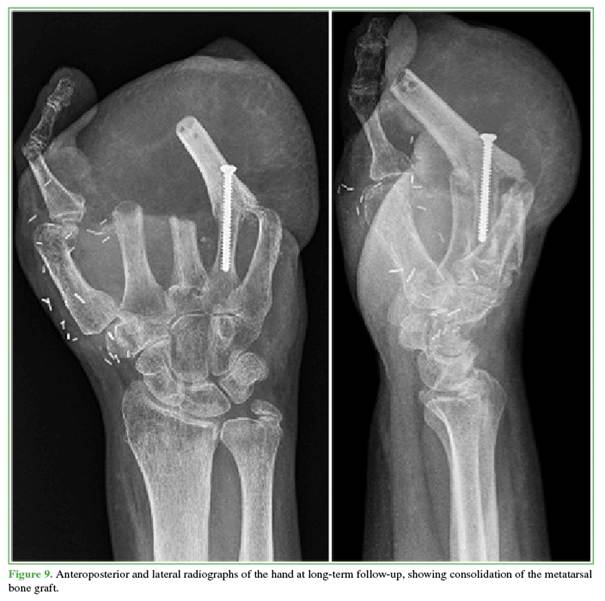

The metatarsal graft shows clinical and radiographic signs of consolidation (Figure 9).